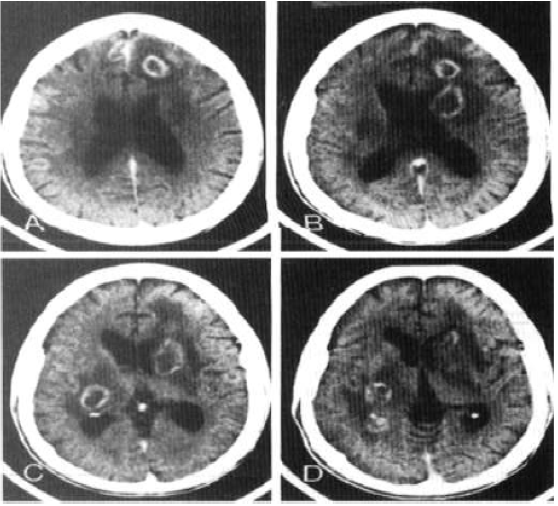

Sr. FS, 39 anos, convive com HIV há 10 anos, faz uso irregular de terapia antirretroviral e não sabe referir seu último CD4 dosado. Ele procura atendimento no pronto-socorro por quadro de rebaixamento do nível de consciência há três dias, associado à intensa cefaleia. Apresentou três episódios de convulsões tônico-clônicas generalizadas. O exame neurológico simplificado demonstrou hemiparesia à esquerda, Glasgow 13, sem sinais de irritação meníngea e com fundo de olho normal. Foi realizada tomografia, de acordo com a imagem a seguir:

enunciado 1960521-1

Considere que a principal hipótese diagnóstica foi confirmada. Qual deve ser a conduta CORRETA?